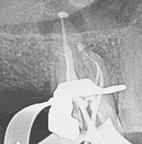

Clinical case performed by Dr. Benedict Bachstein (Figures 1-3)

The patient was diagnosed with irreversible pulpitis in tooth number 14, which presented multiple canals with highly complex anatomies. All canals were instrumented to 25/.04 and cleaned with Odne®Clean following the recommended clinical protocol. The use of Odne®Clean enabled the identification of five canal orifices and clearing of apical deltas.